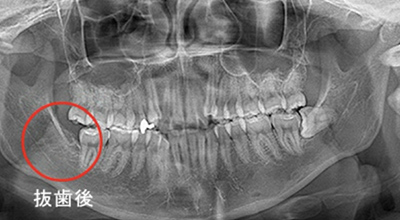

親知らずの抜歯

(難抜歯対応可能)

大人の歯が、歯ぐきや歯槽骨の中に埋まっている状態が埋伏歯と呼ばれます。必要があれば、歯茎を切開して歯を取り出します。埋伏歯の周りの神経や血管の位置によっては、一般的な抜歯と比べはるかに高い技術が要求されます。

親知らずの難症のケース

治療症例